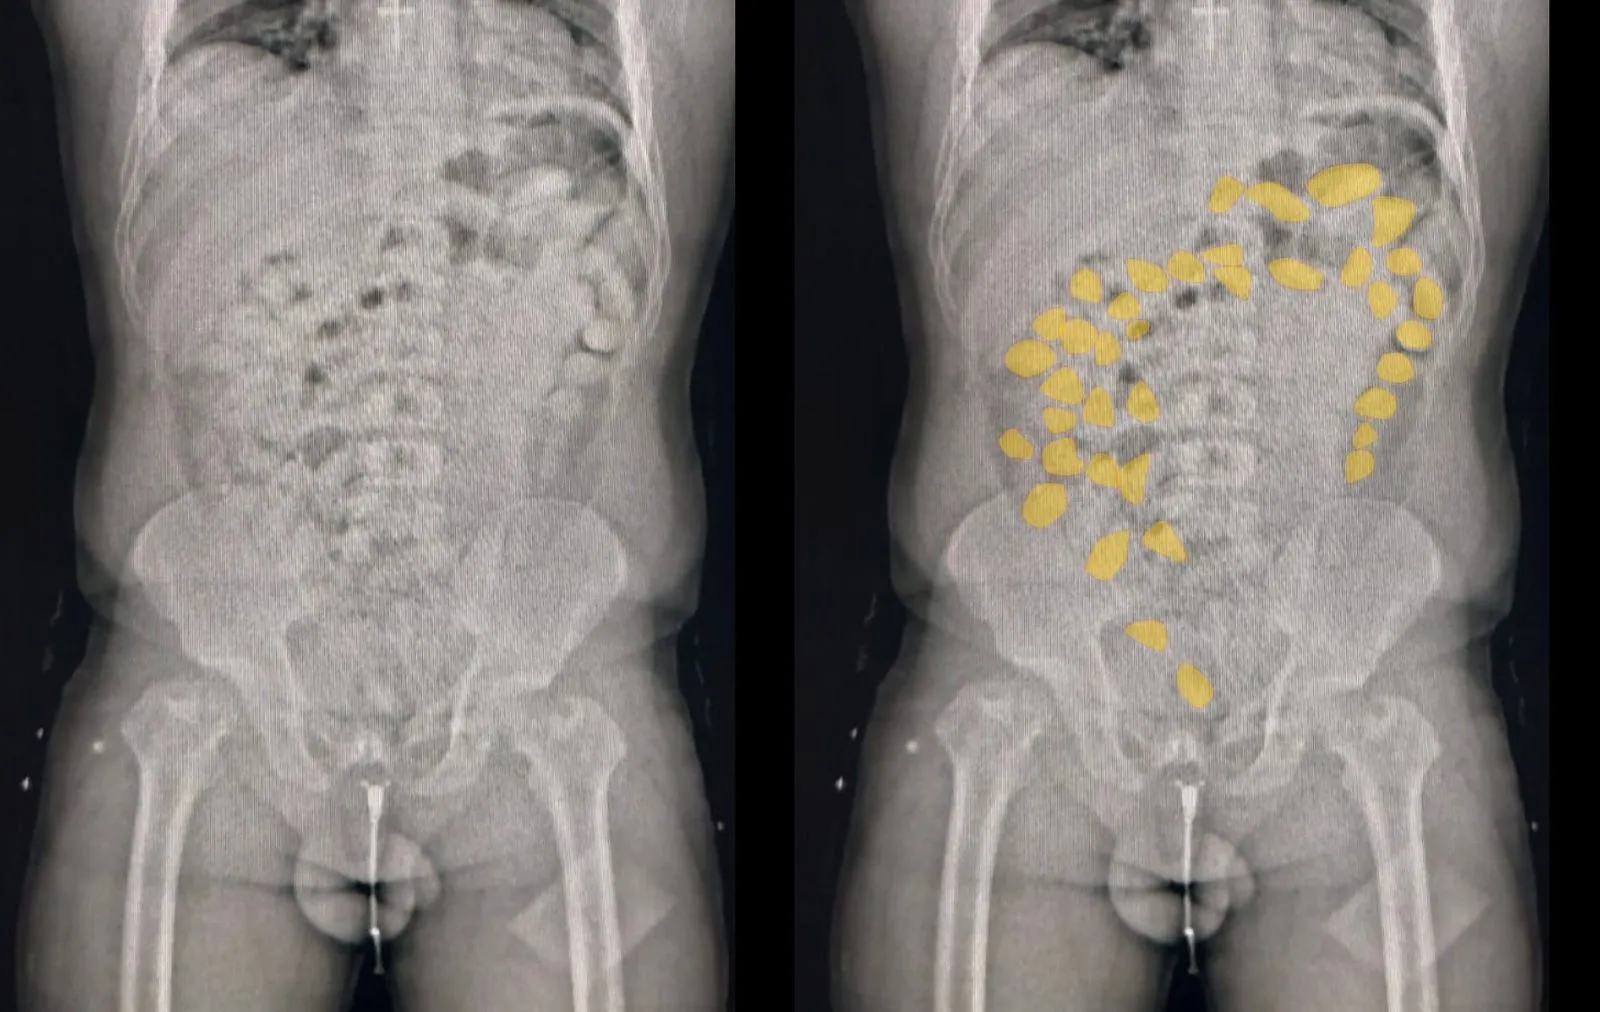

Los agentes de seguridad detuvieron el ómnibus de la empresa Flecha Bus para un control de rutina. Las sospechas cayeron sobre dos pasajeros, a quienes, tras una inspección inicial, encontraron 30 cápsulas de cocaína escondidas en un bolsillo, con un peso de 330 gramos. Ante la posibilidad de que la droga estuviera siendo transportada bajo la modalidad de «mula» —ingerida en cápsulas—, decidieron trasladar a los detenidos a un centro de salud.